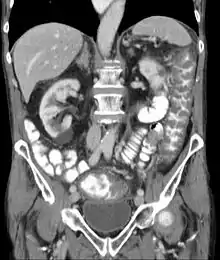

عدوى المطثية العسيرة أو التهاب القولون الغشائي الكاذب أو الاسهال المرتبط بالمطثية العسيرة أو التهاب القولون بالمطثية العسيرة أو عدوى الكلوستريديوم ديفيسيل[3] (بالإنجليزية: Pseudomembranous colitis) هي أحد مسببات الإسهال المتعلق بالمضادات الحيوية، وهي عبارة عن التهاب القولون. وهذا الالتهاب في الأغلب وليس دائماً يحدث بسبب بكتيريا المطثية العسيرة. ولهذا يمكن ان يسمى المرض أيضاً بالتهاب قولون المطثية العسيرة.

قبل ظهور اختبارات للكشف عن سموم المطثية العسيرة، سابقاً كان تشخيص التهاب القولون الغشائي الكاذب عن طريق تنظير القولون أو تنظير السيني. المظهر "الغشائي الكاذب" على الغشاء المخاطي للقولون أو المستقيم هو مشخص لالتهاب القولون الغشائي الكاذب. ويتكون "الغشاء الكاذب" من إفرازات مصنوعة من بقايا الإتهابات، وخلايا الدم البيضاء وغيرها.